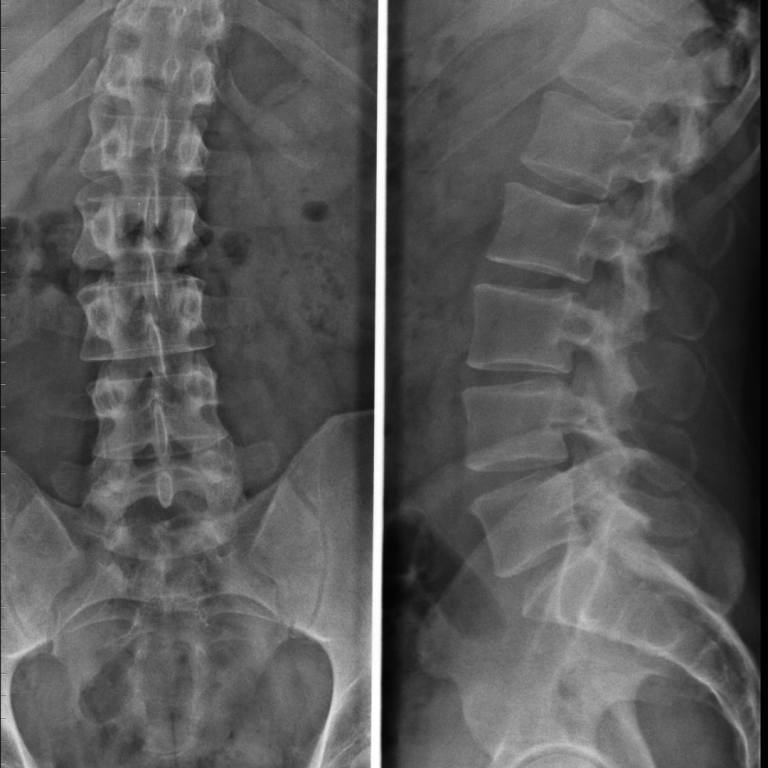

Radiografie:

• Ce poți evalua: aliniament, scolioză, cifoze/lordoze, spondilolistezis

• Când este utilă radiografia dinamică (flexie–extensie)

Lecția 7 – Scolioza: structură, rotație și implicații funcționale

• Scolioza idiopatică

• Scolioza degenerativă la adult

• Unghiul Cobb (explicat practic)

• Rotația vertebrală

• Deformările compensatorii

• Diferența între scolioză structurală și atitudine scoliotică

• Când există risc neurologic asociat

Obiectiv: să înțelegi când deformarea este doar posturală și când este structurală cu implicații mecanice reale.